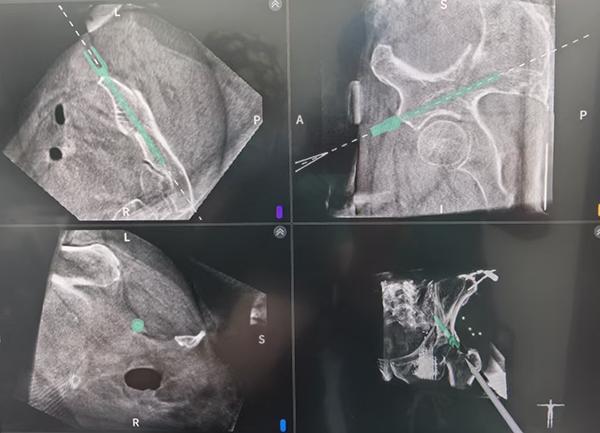

手术前,团队通过三维CT扫描获取骨盆精准影像,在电脑上规划出最佳的螺钉置入路径。骨科手术机器人接收指令后,机械臂精确定位,仅通过两个硬币大小的微创切口(约1.5厘米),在实时引导下顺利完成了髂骨螺钉及LC‑Ⅱ螺钉的置入。整个手术不到2小时,出血量仅约10毫升。

“骨盆结构就像一个复杂的‘迷宫’,周围布满神经和血管,传统手术全靠医生经验和手感,稍有不慎就可能造成严重损伤。” 何晓宇介绍,骨科手术机器人实现了从“凭经验”到“可视化精准操作”的跨越,能清晰看到每一步操作的位置,最大限度避免损伤重要组织,同时缩短手术时间、减少并发症,让患者更快回归正常生活。